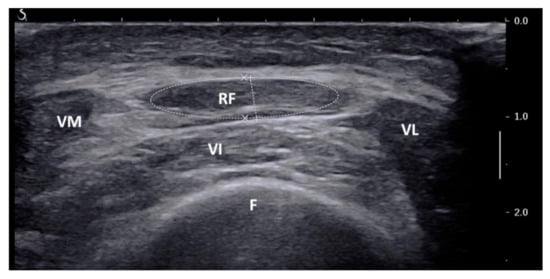

2.2. Ultrasound of Rectus Femoris

- US-defined rectus femoris CSA: 1.32 cm2 (sensitivity 82%, specificity 62%, VPP 55%, VPN 87%; prevalence of low SMM: 54%, 35/65);